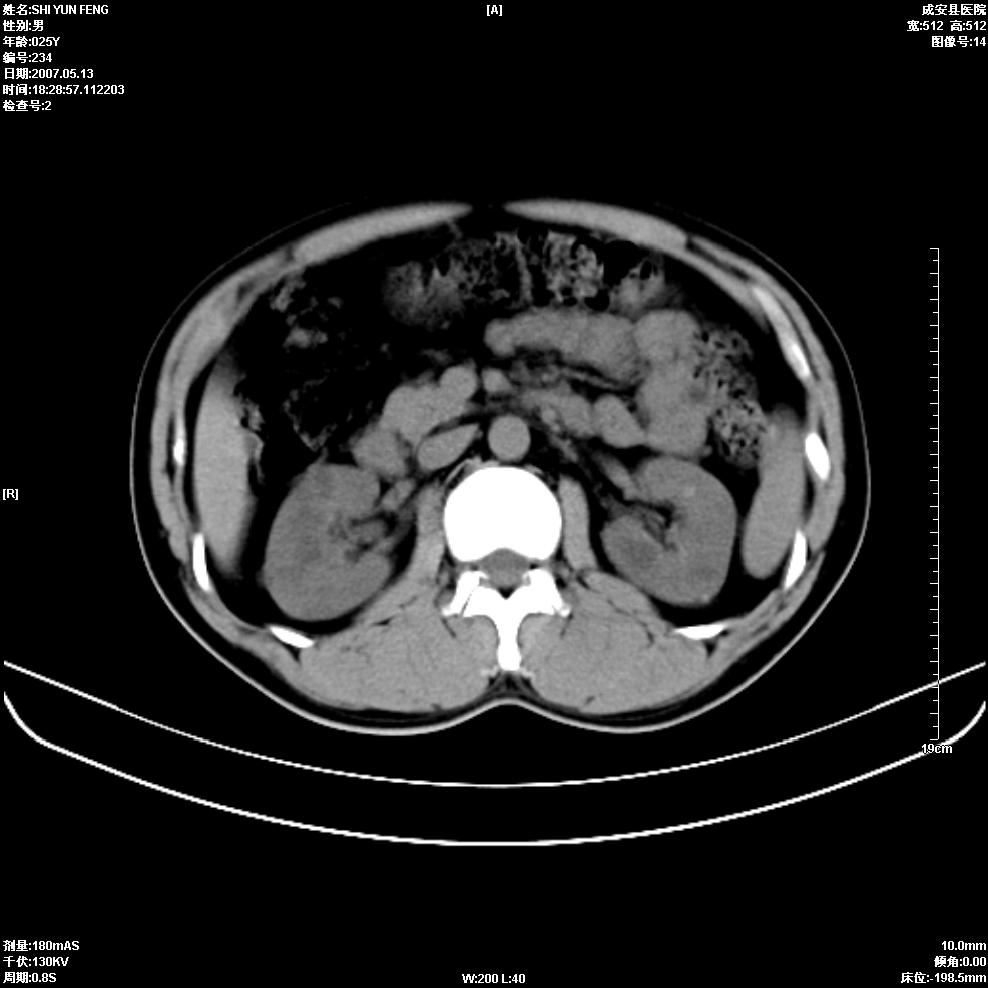

以下是引用zhangzhongshou在2007-5-16 7:36:00的发言:[br]多发性肾囊肿,左肾多发结石。不是多囊肾,楼主箭头所指多考虑左肾囊肿内结石或钙乳,髓质海绵肾不完全除外。[br][br][本贴已被 zhangzhongshou 于 2007-5-16 7:37:18 修改过][br][br][本贴已被 zhangzhongshou 于 2007-5-16 18:15:09 修改过]